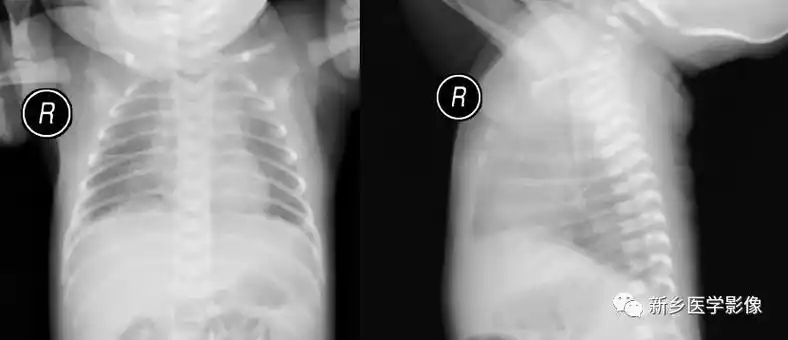

新生儿肺纹理粗不一定是肺炎,有可能是:新生儿湿肺